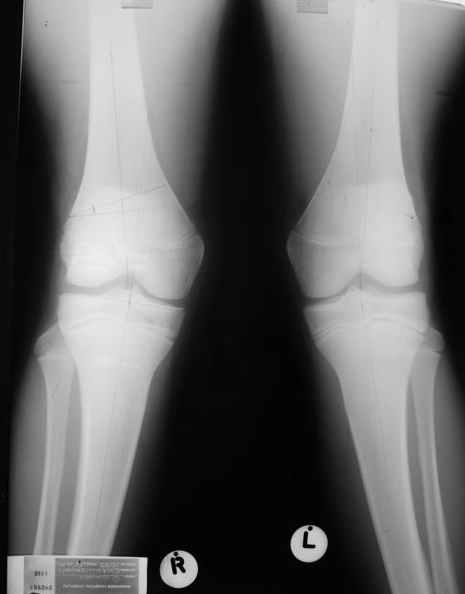

Уважаемый Евгений ! Спасибо за ответ, но мне представляется, что в нашем случае основной проблемой является не столько прогрессирующий вальгус конечности, сколько несросшийся перелом мыщелка бедра и дефект мыщелка большеберцой кости - вероятно первичная репозиция выполнялась без пластики.

Относительно "рубцовой подушки" я имел в виду остатки мениска ( частично вколоченного в дефект мыщелка и фрагменты хряща), все таки на рентгенограммах суставная щель в этом отделе чем то заполнена. Что касается некроза мыщелка бедра, то мне кажется он уже наступил - томограмма ноябрь5.

С учетом всего сказанного - наличия прогессирующего вальгуса конечности, довольно приличного объема движений, имеющегося, вероятно, некроза мыщелка бедра, наиболее рациональным представляется удалить пластину с б\б кости, произвести остеотомию б\б кости с коррекцией вальгуса, разгрузив тем самым наружный отдел сустава, и синтезировать фрагменты голени накостным фиксатором. Максимально тано начать восстановление движений в суставе. Скорее всего рано или поздно речь о протезировании всеже возникнет, но мы хотя бы будем иметь приличную ось конечности.

Тут ситуация совсем другая. Деформация не около-, а самая что ни на есть внутрисуставная. Покорректировать внешний вид конечности путем остеотомии дистального отдела бедра и high tibia (плюс или минус клин, одномоментно-постепенно, аппарат-пластина-стержень - дело третье) не сильно сложно, но это не решение проблемы. У больной, по

сути отсуствует латеральный отдел коленного сустава, что требует костно-пластических вмешательств непосредственно на артикулирующих

поверхностях.